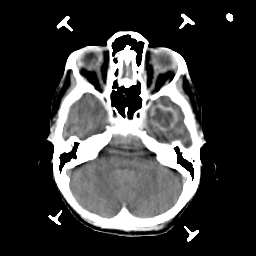

Metastatic bronchogenic carcinoma: Roentgen-ray CT -- Slice #5

[Home][Help][Clinical] Slice 5